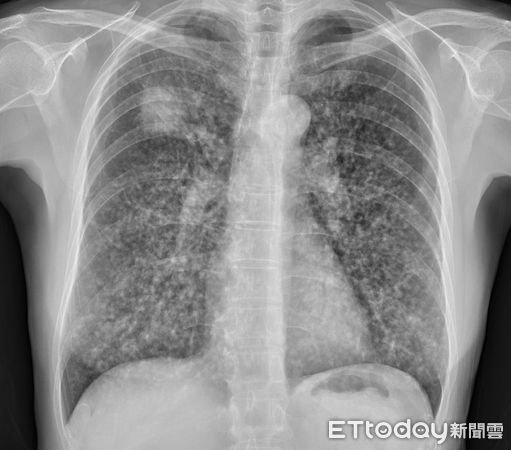

根據《ETtoday》報導,北市聯醫陽明院區胸腔內科主治醫師蘇一峰分享一個案,有一名50多歲的職場女性就醫看診,表示自己近期一直有輕微咳嗽的症狀,原以為是輕微的肺部問題,怎料竟是肺癌末期,甚至已經轉移到體內各處,從X光及電腦斷層檢查來看,肺部整片都是滿天星,白花花一片,醫生也束手無策,生命已開始倒數計時了!

仔細詢問下才知道,這名患者3年多前參加員工體檢時,就曾X光照出1公分的肺部結節,但她忙著工作並不理會它,繼續工作打拚到現在,怎知才3年時間病況就惡化如此快,從X光片能看出左上方肺部已有4、5公分的腫瘤,崩潰表示:「真的只有一點點咳嗽而已......」